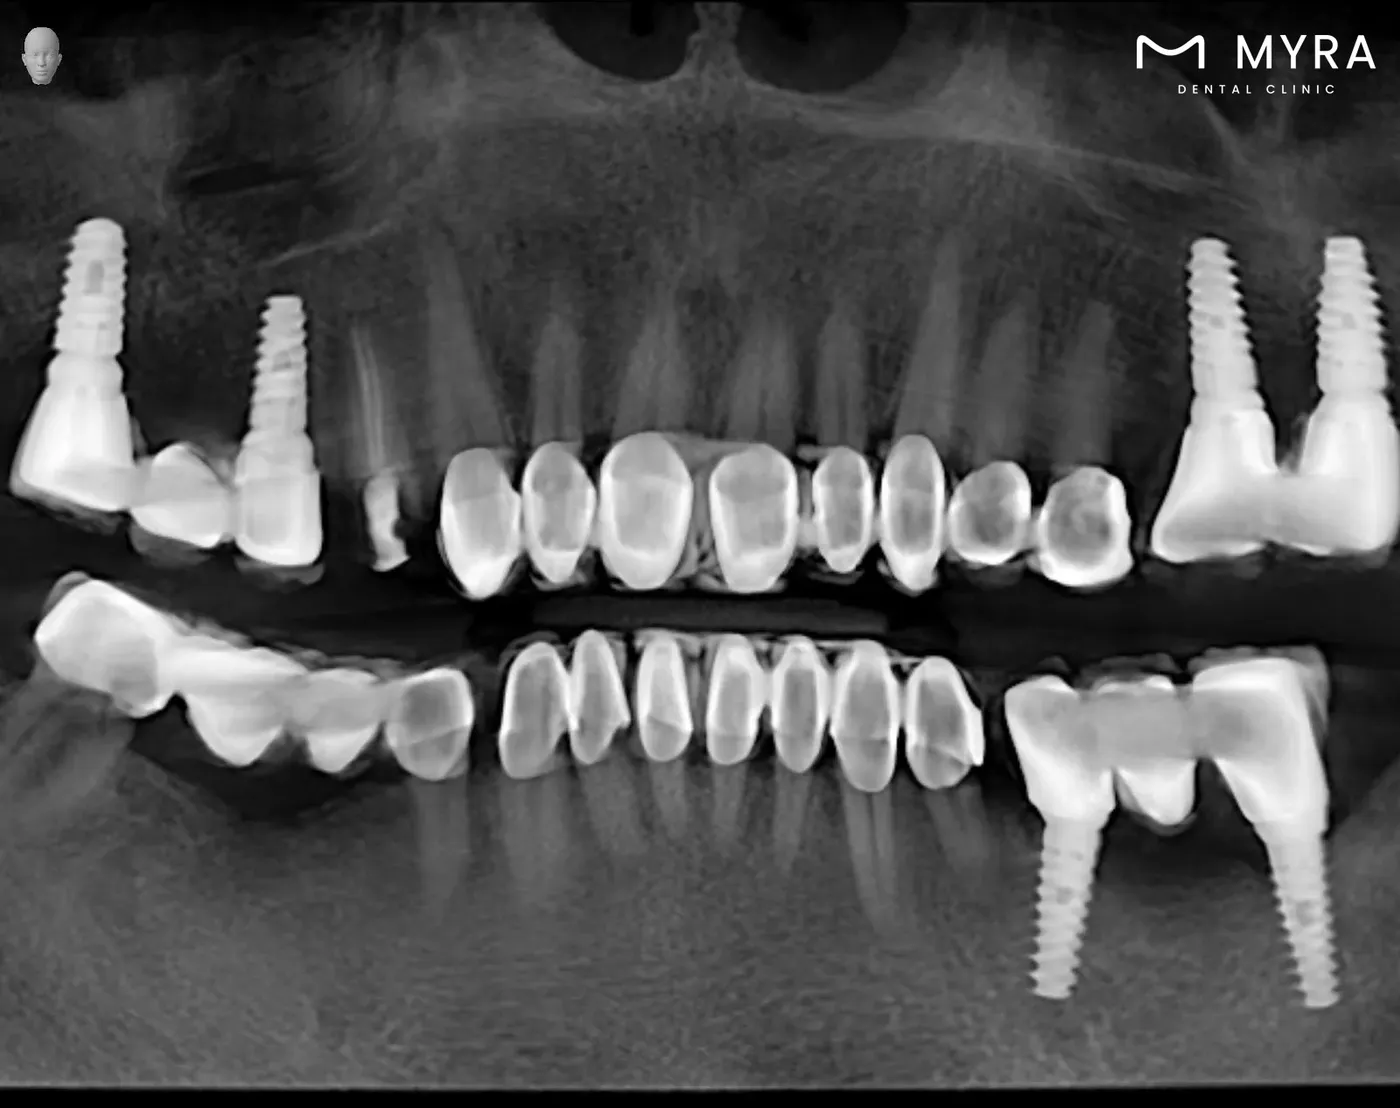

New dentistry software is found integrated into an implant knowledge base. Each brand implant can be added to the simulation by selecting this data. There’s an implant simulation in a patient CT above, and we’re starting processing with this data.

If you can’t figure out which tooth is implanted here, you’ve found a good implant specialist.

You see an example of hybrid prostheses above. İn this system, new teeth can be completed ideally with 7 upper 7 lower implants. The most important advantage of this system is that it is fixed and cannot be removed.